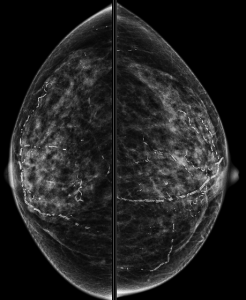

In this patient’s case, there is gradual involution (and slowly increasing calcifications) of this fibroadenoma (image on the left) compared to mammogram five years prior (image on the right):